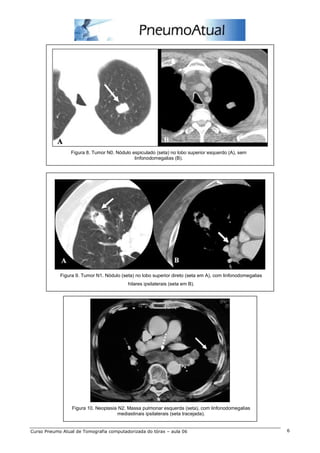

Figura 8. Tumor N0. Nódulo espiculado (seta) no lobo superior esquerdo (A), sem

linfonodomegalias (B).

Figura 9. Tumor N1. Nódulo (seta) no lobo superior direto (seta em A), com linfonodomegalias

hilares ipsilaterais (seta em B).

Figura 10. Neoplasia N2. Massa pulmonar esquerda (seta), com linfonodomegalias

mediastinais ipsilaterais (seta tracejada).